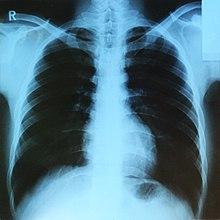

DICOM(Digital Imaging and Communications in Medicine)은 표준 의료영상/기록 포맷이다:

- 주로 병원 내 'PACS(Picture, Archive, Communications)' 시스템에 의해 처리된다.

- 현재 거의 대부분의 의료영상기록이 DICOM 포맷으로 저장된다.

- X-ray, CT, MRI 등 다양한 의료 영상 데이터를 포함한다.

Figure 1.22 X-ray 영상 - 의료 영상의 기본적인 형태